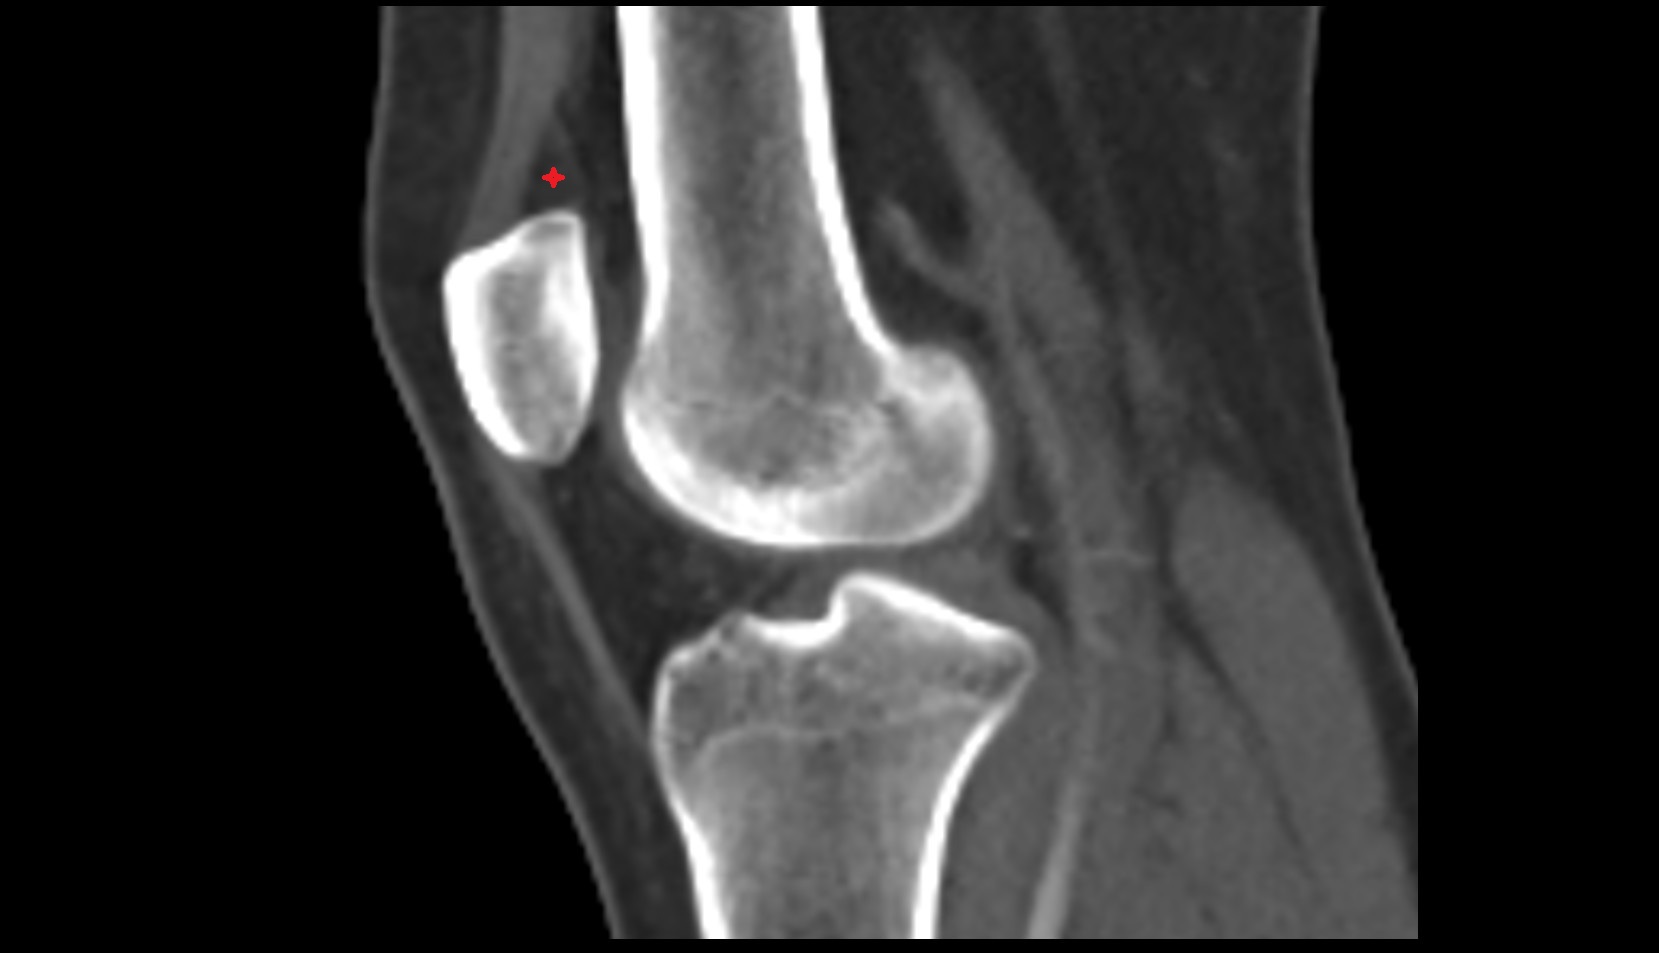

- Medial epicondyle of femur

- Lateral epicondyle of femur

- Lateral condyle of femur

- Medial condyle of femur

- Femoral condyle articular cartilage

- Tibial condyle articular cartilage

- Tibia

- Fibula

- Head of fibula

- Patella

- Knee Joint